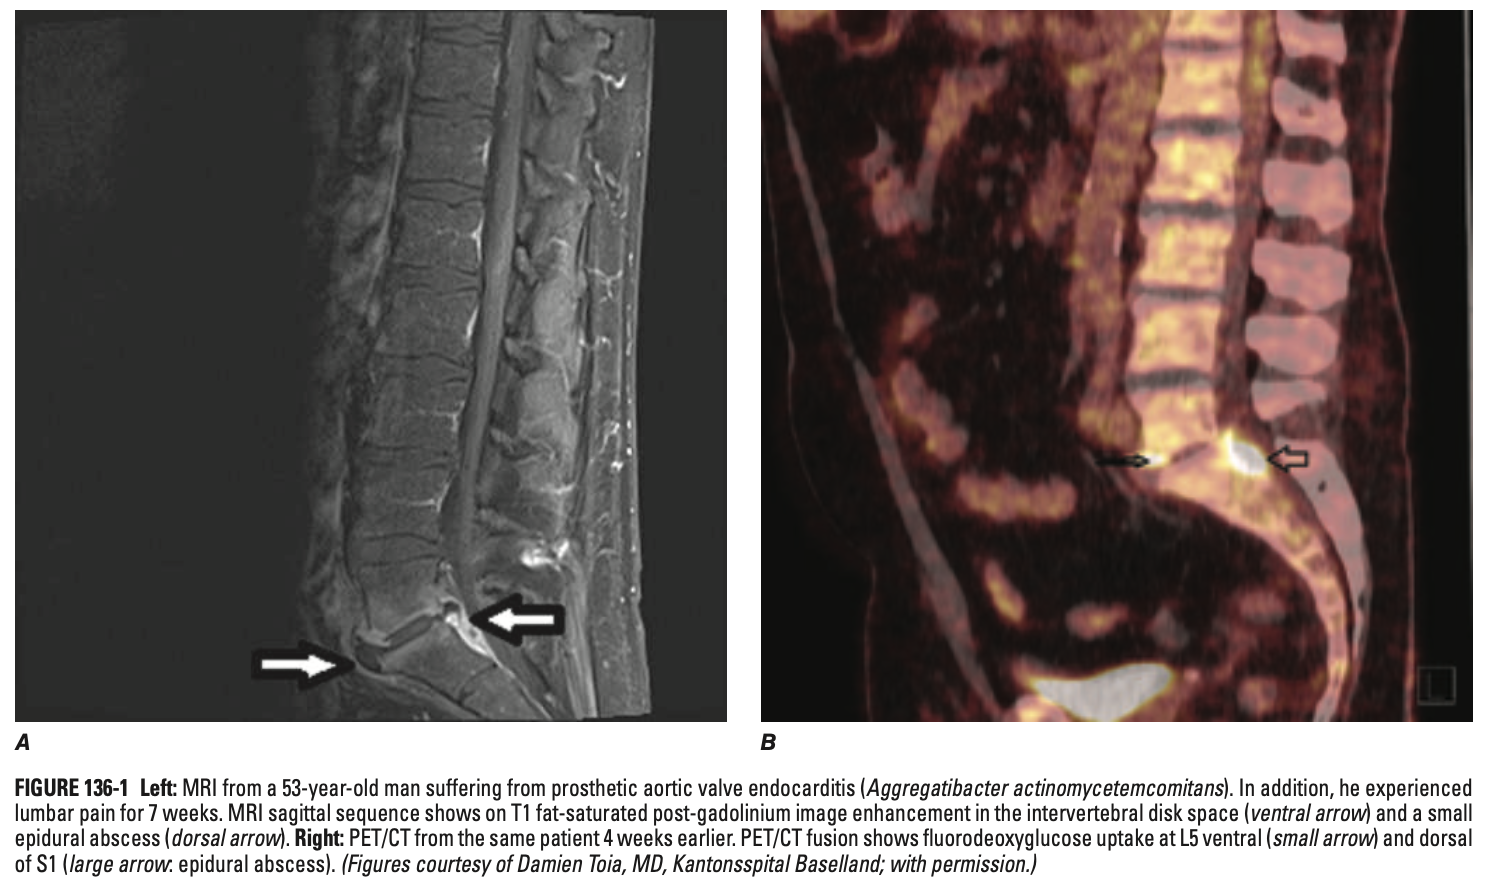

• MRI: 가장 민감하고 특이적인 영상 검사 (Early diagnosis)